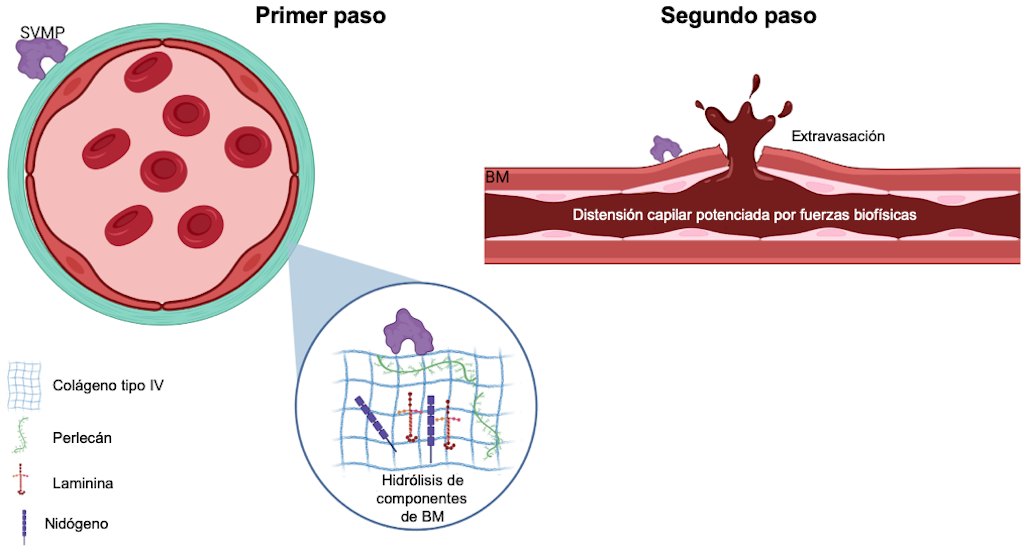

Esta actividad puede ser local o sistémica y depende del catalizador. Se ha propuesto una hipótesis de dos pasos para explicar cómo estas toxinas inducen hemorragia [52]. Inicialmente, las SVMP hidrolizan el sustrato en la membrana basal (MB), como el colágeno tipo IV, la laminina, el nidógeno y el perlecán. Esto debilita la estabilidad mecánica de la MB y aumenta la distensibilidad de la pared del microvaso. Además, las SVMP pueden degradar otras proteínas, incluidas aquellas implicadas en la unión de la MB a la matriz extracelular de los músculos, como los colágenos no fibrilares VI, XII, XIV, XV, XVI y XIX, así como el colágeno fibrilar tipo V [53,62,63].

En el segundo paso, las fuerzas hemodinámicas actúan sobre la microvasculatura, incluida la tensión de corte y la presión hidrostática sobre la pared del microvaso. Estas fuerzas potencian la distensión de la pared, provocando su ruptura y la extravasación de glóbulos rojos [58] (Figura 5).

Figura 5. Representación esquemática del modelo de dos pasos para la hemorragia inducida por SVMP. El primer paso implica la hidrólisis de componentes de la membrana basal (MB) que desestabiliza la interacción entre las células endoteliales y la MB. En el segundo paso, las fuerzas biofísicas contribuyen a la potenciación de la distensión capilar de la pared de los microvasos, lo que lleva a su alteración. Para más detalles, consulte el texto. Imagen creada con Bio Render.